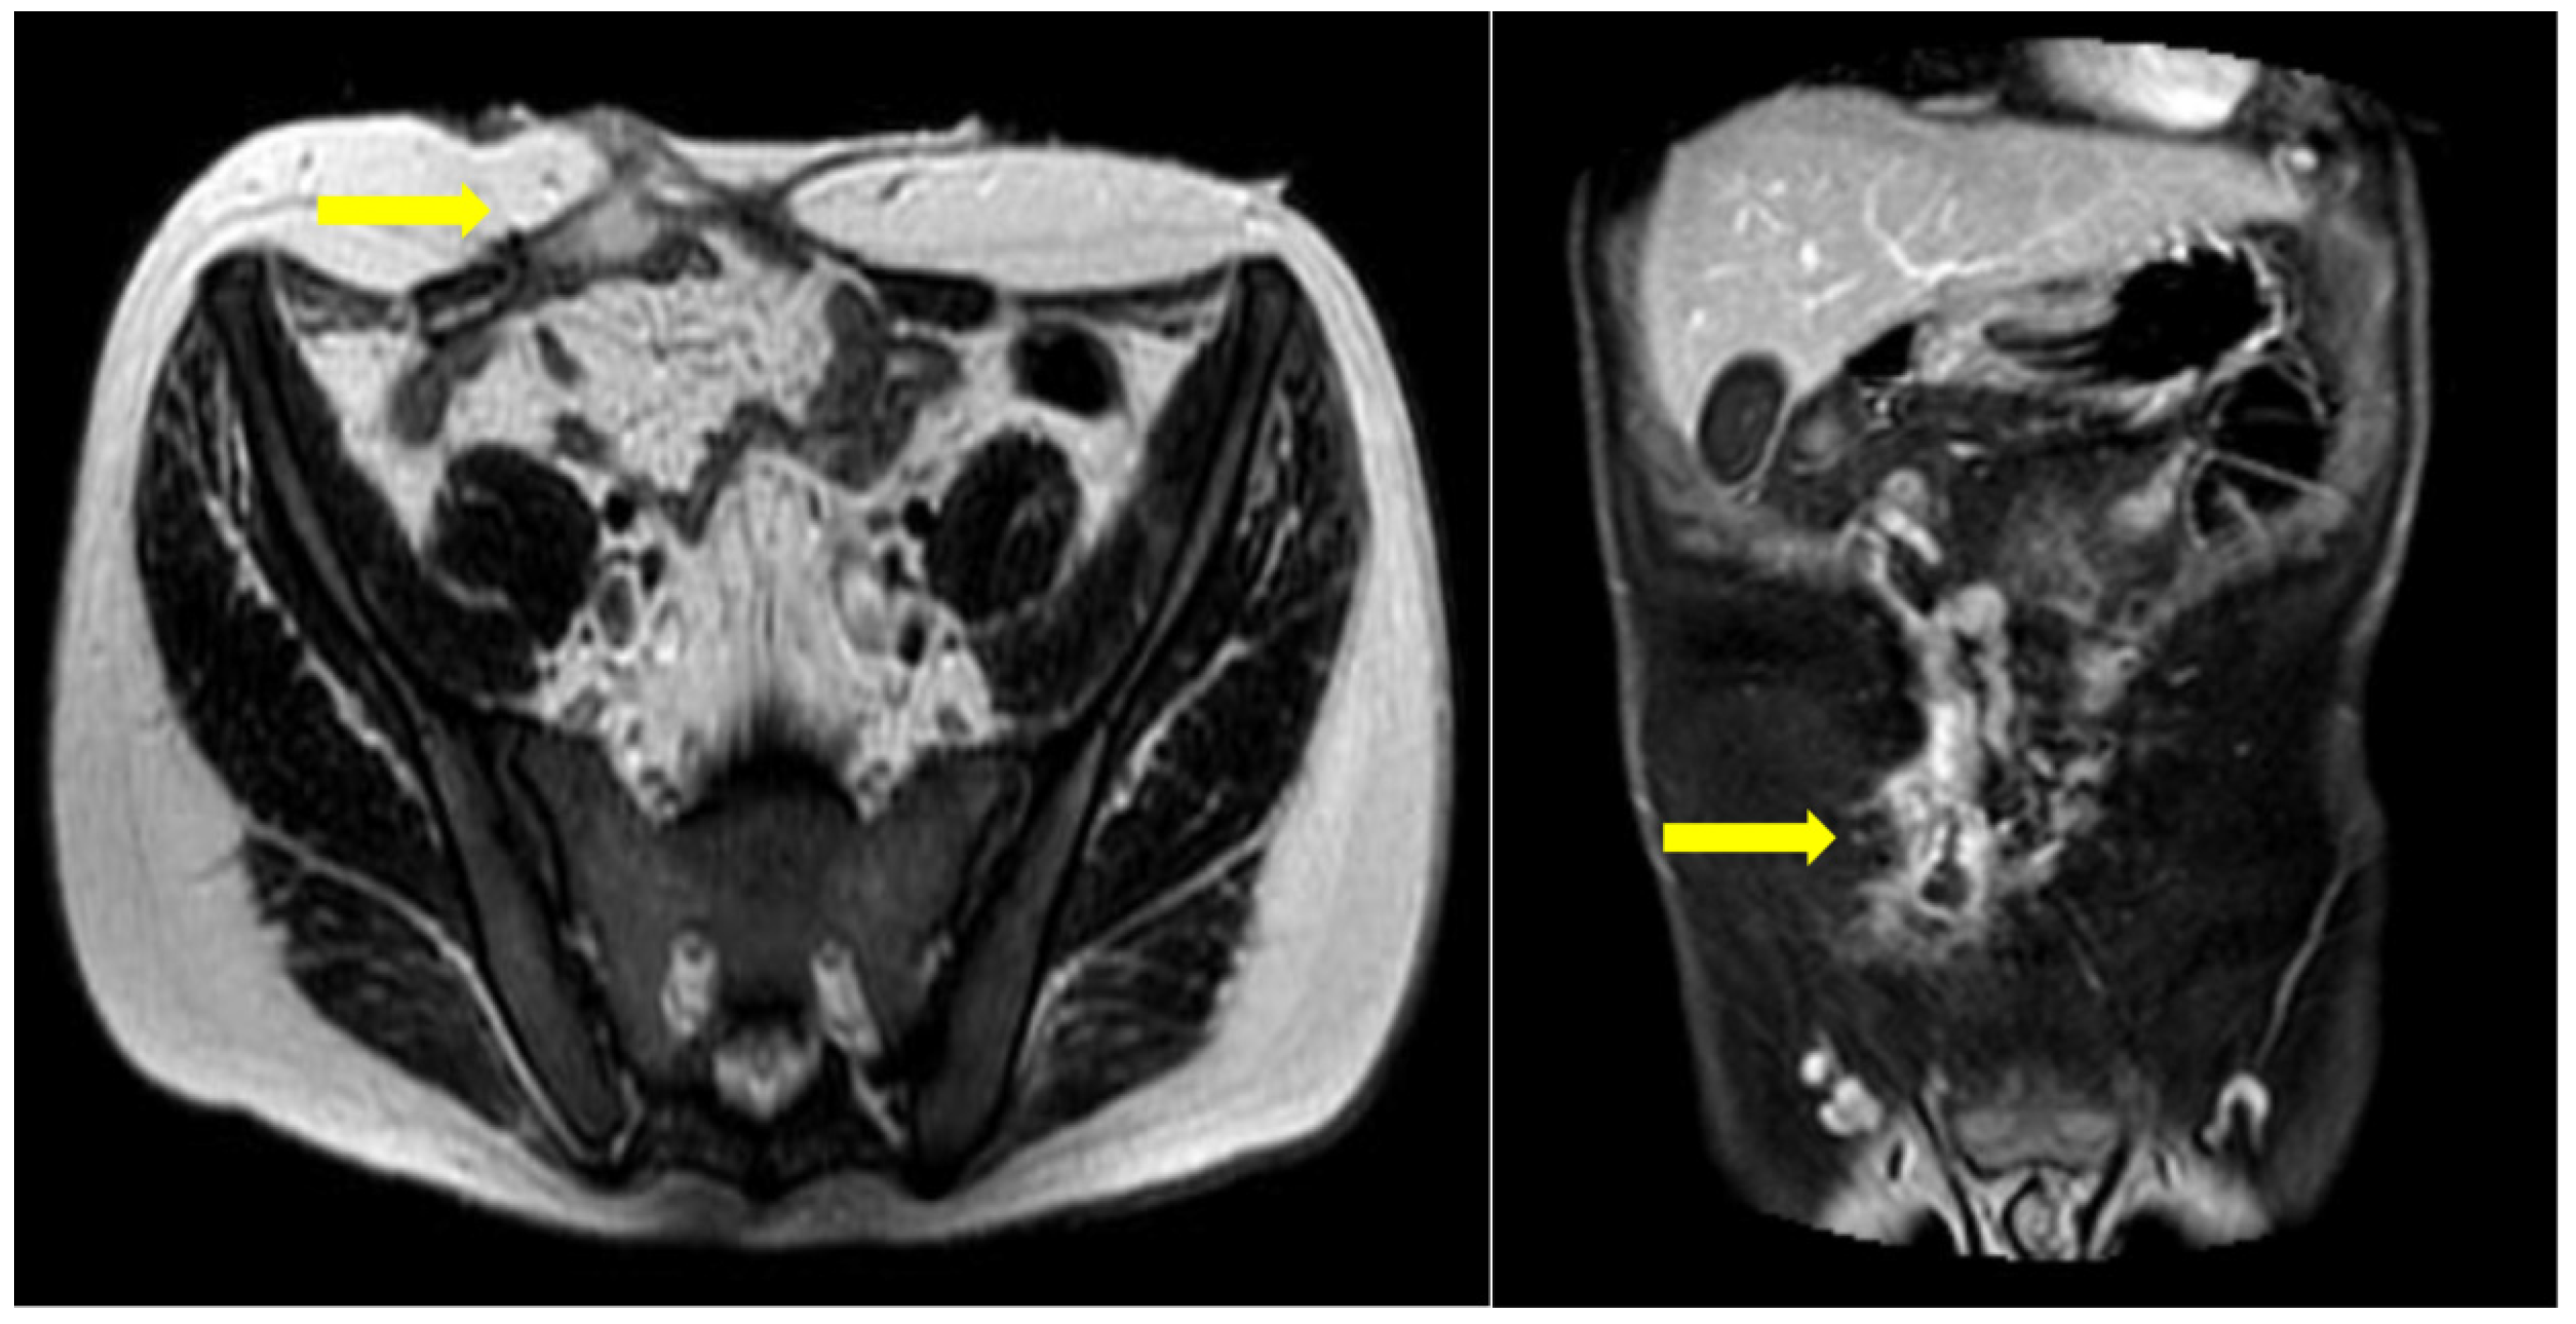

Figure 3. MRI enterography for follow-up. A gap in the anterior abdominal wall is seen, following open surgery with enterectomy. A peripherally enhancing fluid collection is seen juxtapositioned to the rectus abdominis muscle, in close connection with a collapsed ileal loop. This appearance is in keeping with a fistulous tract between adjacent bowel loops and the anterior wall.

Six months postoperatively, the patient was referred to our department for further diagnostic management and treatment of the remaining enterocutaneous fistula (Figure 1). A variety of diagnostic tests (hematological, endocrinological, gastrointestinal) and multiple imaging examinations were performed. There were no abnormal findings, except for vitamin Κ deficiency, as expected in the context of chronic non-intestinal feeding. The Magnetic Resonance Imaging (MRI) enterography confirmed the presence of a fistula between the jejunum and the skin, with the internal stoma of the fistula at a distance of about 65-70cm from the Treitz (Figure 3). Therefore, given that the patient has a functional bowel slightly more than half a meter in length, the diagnosis of short bowel syndrome with the accompanying problems of malnutrition was established.